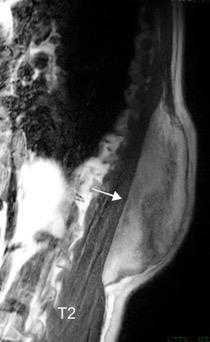

Tumor desmoide (“Fibromatosis agresiva”)

T1: Isointensos con músculos.

T2: Señal intermedia y de alta intensidad.

Presencia frecuente de áreas curvilíneas y lineales dentro de la lesión

Mansour J et al. Diagnostic and Imaging Approaches to Chest Wall Lesions. Radiographics 2022